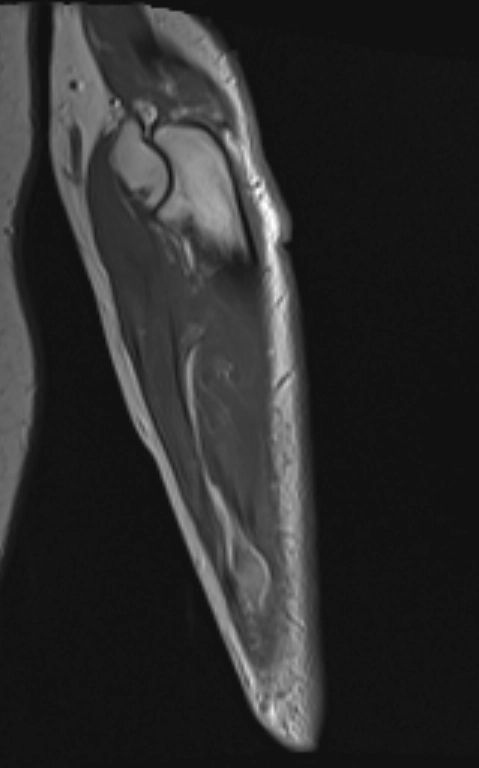

U thần kinh do chấn thương (Traumatic neuroma)